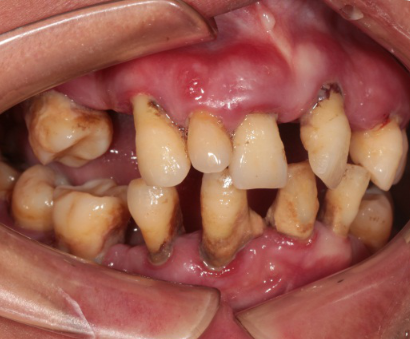

Intraoral Examination(A zone=Right upper jaw、B zone=Left upper jaw、C zone=Left lower jaw、D zone=Right lower jaw)

Poor oral hygiene, accumulation of calculus, three-degree loosening of the entire mouth

Periodontitis causes severe absorption of the upper and lower jaws

A zone A4-A6、B zone B2、C zone C2-C4、D zone D2-D3 lost

A zone A1-A3、A7、B zone B1、B5-B7、C zone C1、C5-C7、D zone D1、D4-D8 all with III°loosen

Photos of preliminary oral diagnosis